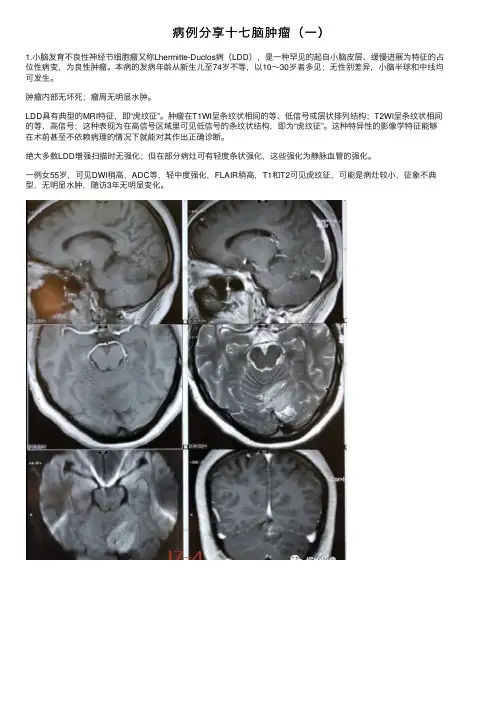

病例分享⼗七脑肿瘤(⼀)1.⼩脑发育不良性神经节细胞瘤⼜称Lhermitte-Duclos病(LDD),是⼀种罕见的起⾃⼩脑⽪层、缓慢进展为特征的占位性病变,为良性肿瘤。

本病的发病年龄从新⽣⼉⾄74岁不等,以10~30岁者多见;⽆性别差异,⼩脑半球和中线均可发⽣。

肿瘤内部⽆坏死;瘤周⽆明显⽔肿。

LDD具有典型的MRI特征,即“虎纹征”。

肿瘤在T1WI呈条纹状相间的等、低信号或层状排列结构;T2WI呈条纹状相间的等、⾼信号;这种表现为在⾼信号区域⾥可见低信号的条纹状结构,即为“虎纹征”。

这种特异性的影像学特征能够在术前甚⾄不依赖病理的情况下就能对其作出正确诊断。

绝⼤多数LDD增强扫描时⽆强化;但在部分病灶可有轻度条状强化,这些强化为静脉⾎管的强化。

⼀例⼥55岁,可见DWI稍⾼,ADC等,轻中度强化,FLAIR稍⾼,T1和T2可见虎纹征,可能是病灶较⼩,征象不典型,⽆明显⽔肿,随访3年⽆明显变化。